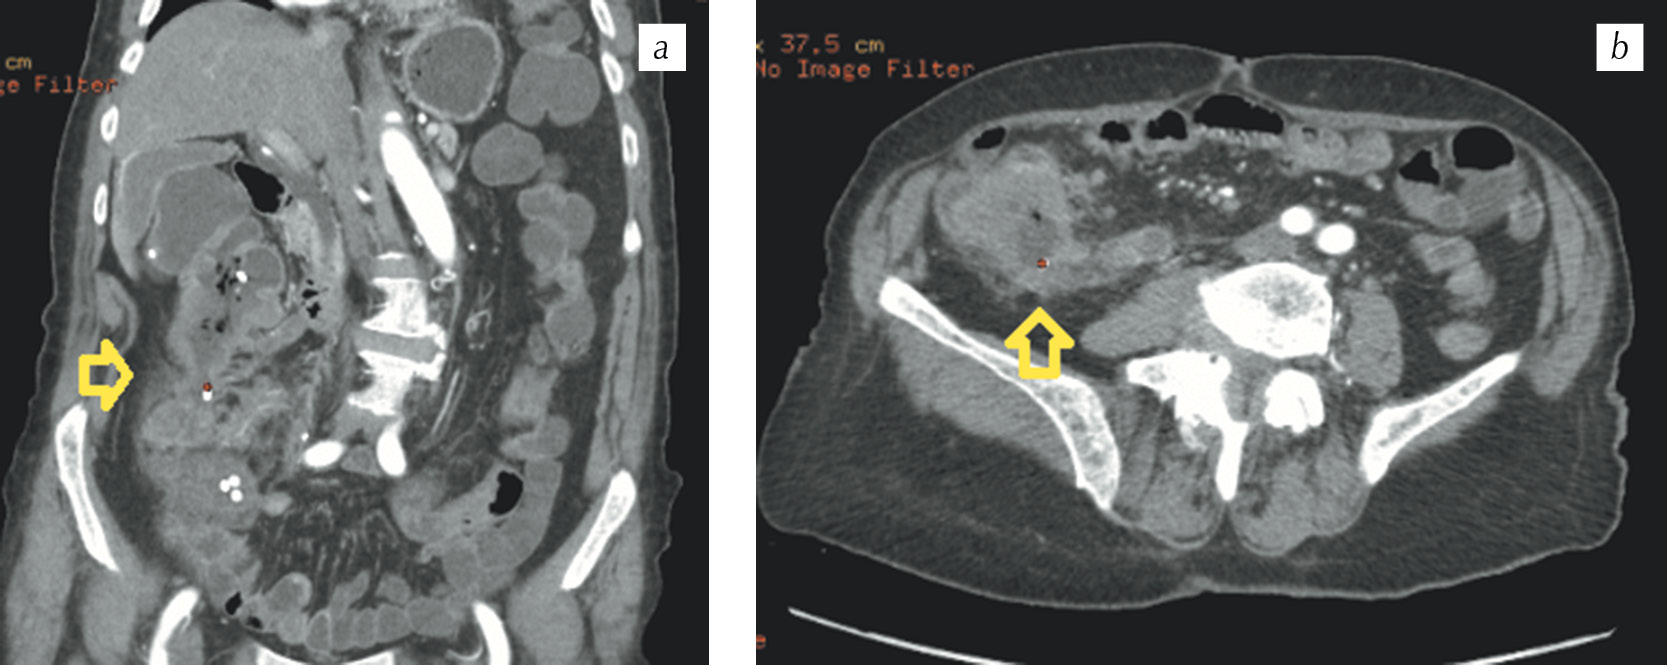

У большинства больных наблюдались третья (33 человека, 44,6 %) и четвертая (24 человека, 32,4 %) стадии онкологического процесса. Всем больным при поступлении проводили комплексное обследование, включавшее рентгенографию груди, живота, ЭКГ, УЗИ, исследование крови, осмотр терапевта. При отсутствии показаний к экстренному оперативному вмешательству объем предоперационного обследования расширяли — проводили эхокардиографию, исследовали функцию внешнего дыхания, выполняли ультразвуковое дуплексное сканирование вен нижних конечностей и др. Более широкое и полноценное обследование позволяло получить исчерпывающую информацию о состоянии основных систем и органов и о степени компенсации сопутствующих заболеваний, а также своевременно корригировать их с привлечением врачей-специалистов смежных специальностей. Большую роль в установлении местнораспространенного опухолевого процесса в толстой кишке играла спиральная компьютерная томография (СКТ) (рис. 1).

Рис. 1. Спиральная компьютерная томография. Мультипланарные реконструкции в корональной (а) и аксиальной (б) проекциях в артериальную фазу. Опухоль восходящей ободочной кишки с инвазией латероканальной фасции и переднего листка почечной фасции (стрелки)

Fig. 1. Spiral computed tomography. Multiplanar reconstructions in the coronal (a) and axial (b) planes into the arterial phase. A tumor of the ascending colon with latero-canal fascia invasion and anterior renal fascia (arrows)